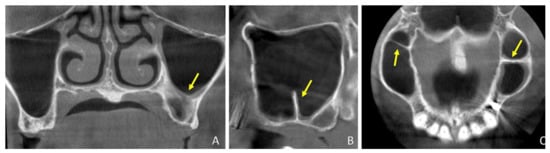

3.2. CBCTs Assessments